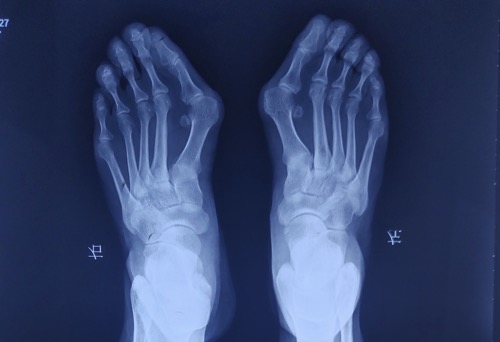

拇外翻的朋友容易在前足长茧子则是因为第一跖骨内翻,然后拇指旋转,第一跖骨旋转,这个时候就会开始出现第一跖骨的上抬,本来在前足有一个人类独有的特点:就是在前足有明显的足横弓。我们很多人知道有足弓,但是大家所说的足弓呢,更多是足内侧纵弓,我们除了足内侧纵弓还有足外侧纵弓,还有一个就是足横弓,很多人可能并不一定知道我们还有个足横弓,足横弓是有第一跖趾关节,第二三四五跖趾关节同时组成了一个拱形的这样的足弓。

当我们人体重快速增加,或者说是体重过重,或者说是同时有拇外翻的时候,就容易出现足横弓的塌陷,出现足横弓塌陷以后,本来应该由第一跖趾关节来承受的重力逐渐转移到了第二第三跖趾关节,这个时候第二三跖趾关节他就需要靠增加至骨头的粗细和增加足底胼胝体的形成来承受这个重力。

第二跖骨过长

当然还有另外一个情况,就是第一跖骨比较短,第二跖骨比较长,这一类人由于先天性的原因,第二跖骨比较长,就容易出现第二跖骨更多的来承重量,这样的人尤其是合并有拇外翻的朋友们:第二跖骨长又合并拇外翻,更容易出现转移性跖骨痛,出现在第二跖趾关节下面的胼胝体。也就是我们看到的拇指比较短,第2个趾头比较长这样的脚型,您看一下您的大拇指和第二指哪个指头比较长,如果说您的第2趾比较长,然后您同时又有拇外翻,这种情况可能更容易出现转移性跖骨痛和出现在第二三跖趾关节下方长茧子。